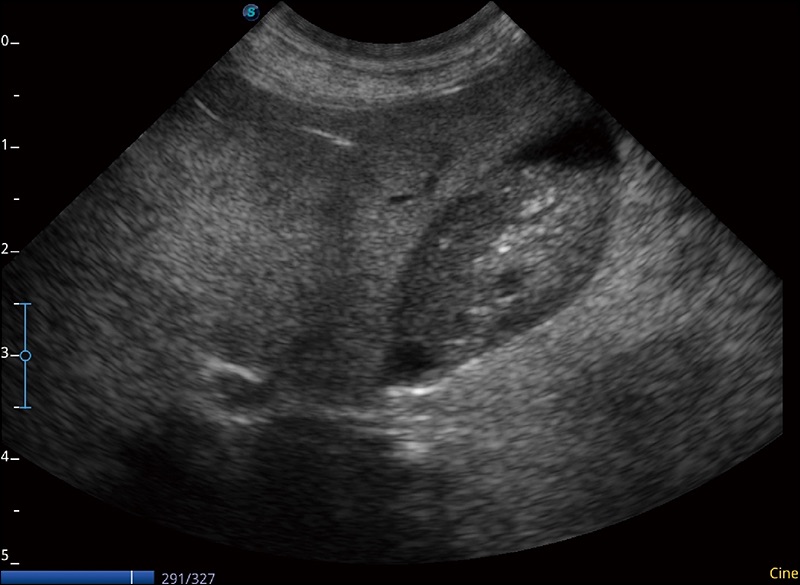

任意波束合成技术

在不牺牲时间分辨率的情况下提供出色的图像